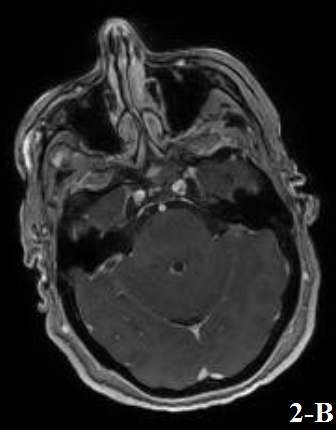

Figure 1 and Figure 2 showed the results of a brain MRI performed at admission, revealing an extensive lesion that involved the periventricular, subcortical and deep white matter.

As a major difference with PCNSL, LC lesions show poor contrast-enhancement, often presenting as ill-defined nodular, periventricular / periependymal enhancement, as what happened in our case (Kitai et al, 2012).

Figure 2. Post-gadolinium enhancement with a nodular pattern found at the level of hypothalamic area (a) and at a periventricular / periependymal level (b).